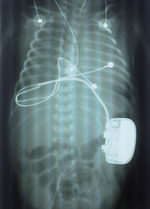

– Wspólnie z neonatologami i kardiologami rozpatrywaliśmy albo szybkie założenie stymulacji czasowej polegającej na podłączeniu elektrod do serca i korzystaniu z zewnętrznego stymulatora w przypadku stanu krytycznego dziecka (do tego zabiegu był przygotowany nasz zespół dyżurny), albo farmakologiczne podtrzymanie funkcji życiowych umożliwiające przyrost masy ciała do ok. 2 kg. Wtedy zabieg implantacji rozrusznika nie byłby już skomplikowany, bo przy takiej wadze dziecka można go już w miarę bezpiecznie wykonać – mówi dr Pająk. Analizując jednak stan zdrowia małego pacjenta i nie najlepsze wyniki rozpoczętego leczenia farmakologicznego, zdecydowano, że najlepszym rozwiązaniem będzie wszczepienie rozrusznika (ryc. 1).

Tak opisuje przebieg operacji: – Zabieg polegał na otwarciu klatki piersiowej i naszyciu na serce dwóch elektrod w taki sposób, by nie uszkodzić jego struktur. Ominęliśmy naczynia wieńcowe i szukaliśmy miejsca, gdzie będzie tylko sam mięsień, co daje pewność, że impuls zbierany z serca i przekazywany na serce będzie miał czysty kontakt z mięśniem sercowym. Przygotowane elektrody podskórnie poprowadziliśmy do miejsca wybranego w powłokach brzusznych, co stanowiło kolejną trudność, ponieważ powłoki te są bardzo cienkie, kilkumilimetrowe, a trzeba w nich wytworzyć specjalną kieszeń i umieścić w niej małą skrzynkę z rozrusznikiem. To trudny technicznie i wymagający precyzji etap zabiegu. W przypadku cienkich, pergaminowych powłok brzusznych istnieje ryzyko przemieszczenia skrzynki nawet do jamy brzusznej, co mogłoby spowodować poważne komplikacje. Kolejne zagrożenie to zbyt płytkie umieszczenie skrzynki mogące prowadzić do martwicy skóry.

Zabieg przebiegał jednak bez powikłań (ryc. 2, 3).

– Rany się zagoiły, nie doszło do zakażenia, przemieszczenia elektrod czy samego rozrusznika, który jest stosunkowo duży w stosunku do wagi pacjenta – dodaje dr Jacek Pająk.

Zaimplantowany rozrusznik różni się od tego wszczepianego dorosłym przede wszystkim rozmiarem. Ten z przeznaczeniem dla najmniejszych pacjentów ma wymiar ok. 20 na 6 mm, jednak pozostałe funkcje są bardzo zbliżone.